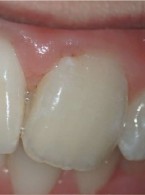

SPECJALISTA RADZI: Wybielanie zębów przebarwionych pastą trójantybiotykową

Podczas jednego z kursów dowiedziałam się, że trójantybiotykową pastę dezynfekującą (TAP) używaną w procedurze rewitalizacji do dezynfekcji kanałów można z powodzeniem stosować w trakcie leczenia zainfekowanych kanałów z zakończonym rozwojem korzenia. Użyłam jej w dwóch przypadkach i w jednych z nich doszło do przebarwienia korony. Czy można taką koronę wybielić i jak to zrobić?